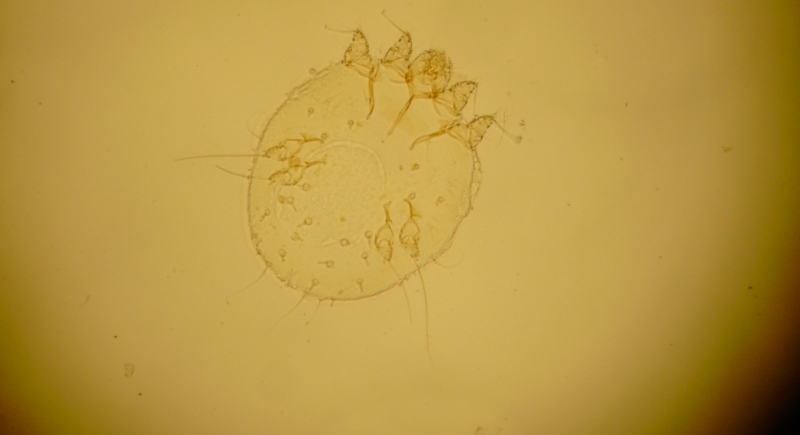

Scabies Mites

Credit: Wikimedia Commons

The scabies mite burrows into the top layer of the skin and lays eggs, which triggers an allergic reaction. Intense itching often worsens at night. The rash appears in areas such as between fingers or around the waist. Prescription creams eliminate the mites, and washing bedding in hot water helps stop reinfestation.